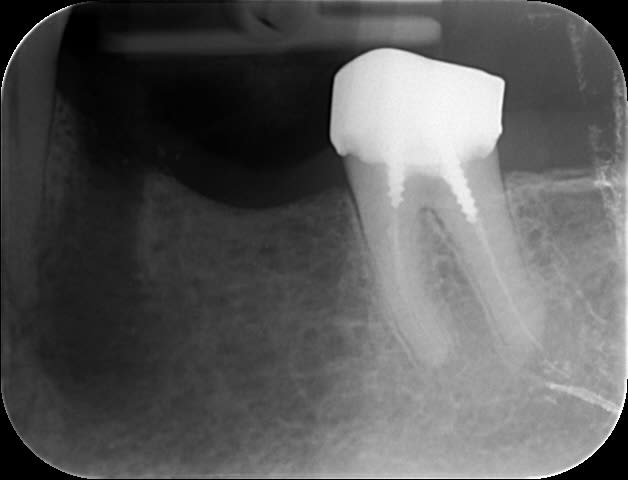

Patient vu à l'instant pour infection traitée il y a 3 semaines sur 35 et joyeux dépassement maintenant douloureux.

Mais j'ai eu un remord : si on curette juste la zone apicale causale, cela doit valoir la peine de tenter la réimplantation.

Moi je l'ai fait. Patiente que j'avais adressé à deux chir pour résection apicale pour une 46, ils ont refusé. Mobilité 3. Beau foyer apical. RTE du tiers apical impossible.

Je me suis souvenu des regles de réimplantation: extraction rapide avec luxation verticale. J'ai prevenu la patiente sur les probabilité de réussite.

Je l'ai extraite, fait la résection apicale dans la main, réimplantée, même pas de contention. Je vous raconte pas les yeux de l'assistante que je n'avais pas prévenu...

Un an après, pas d’ankylose, guérison totale du foyer apical.